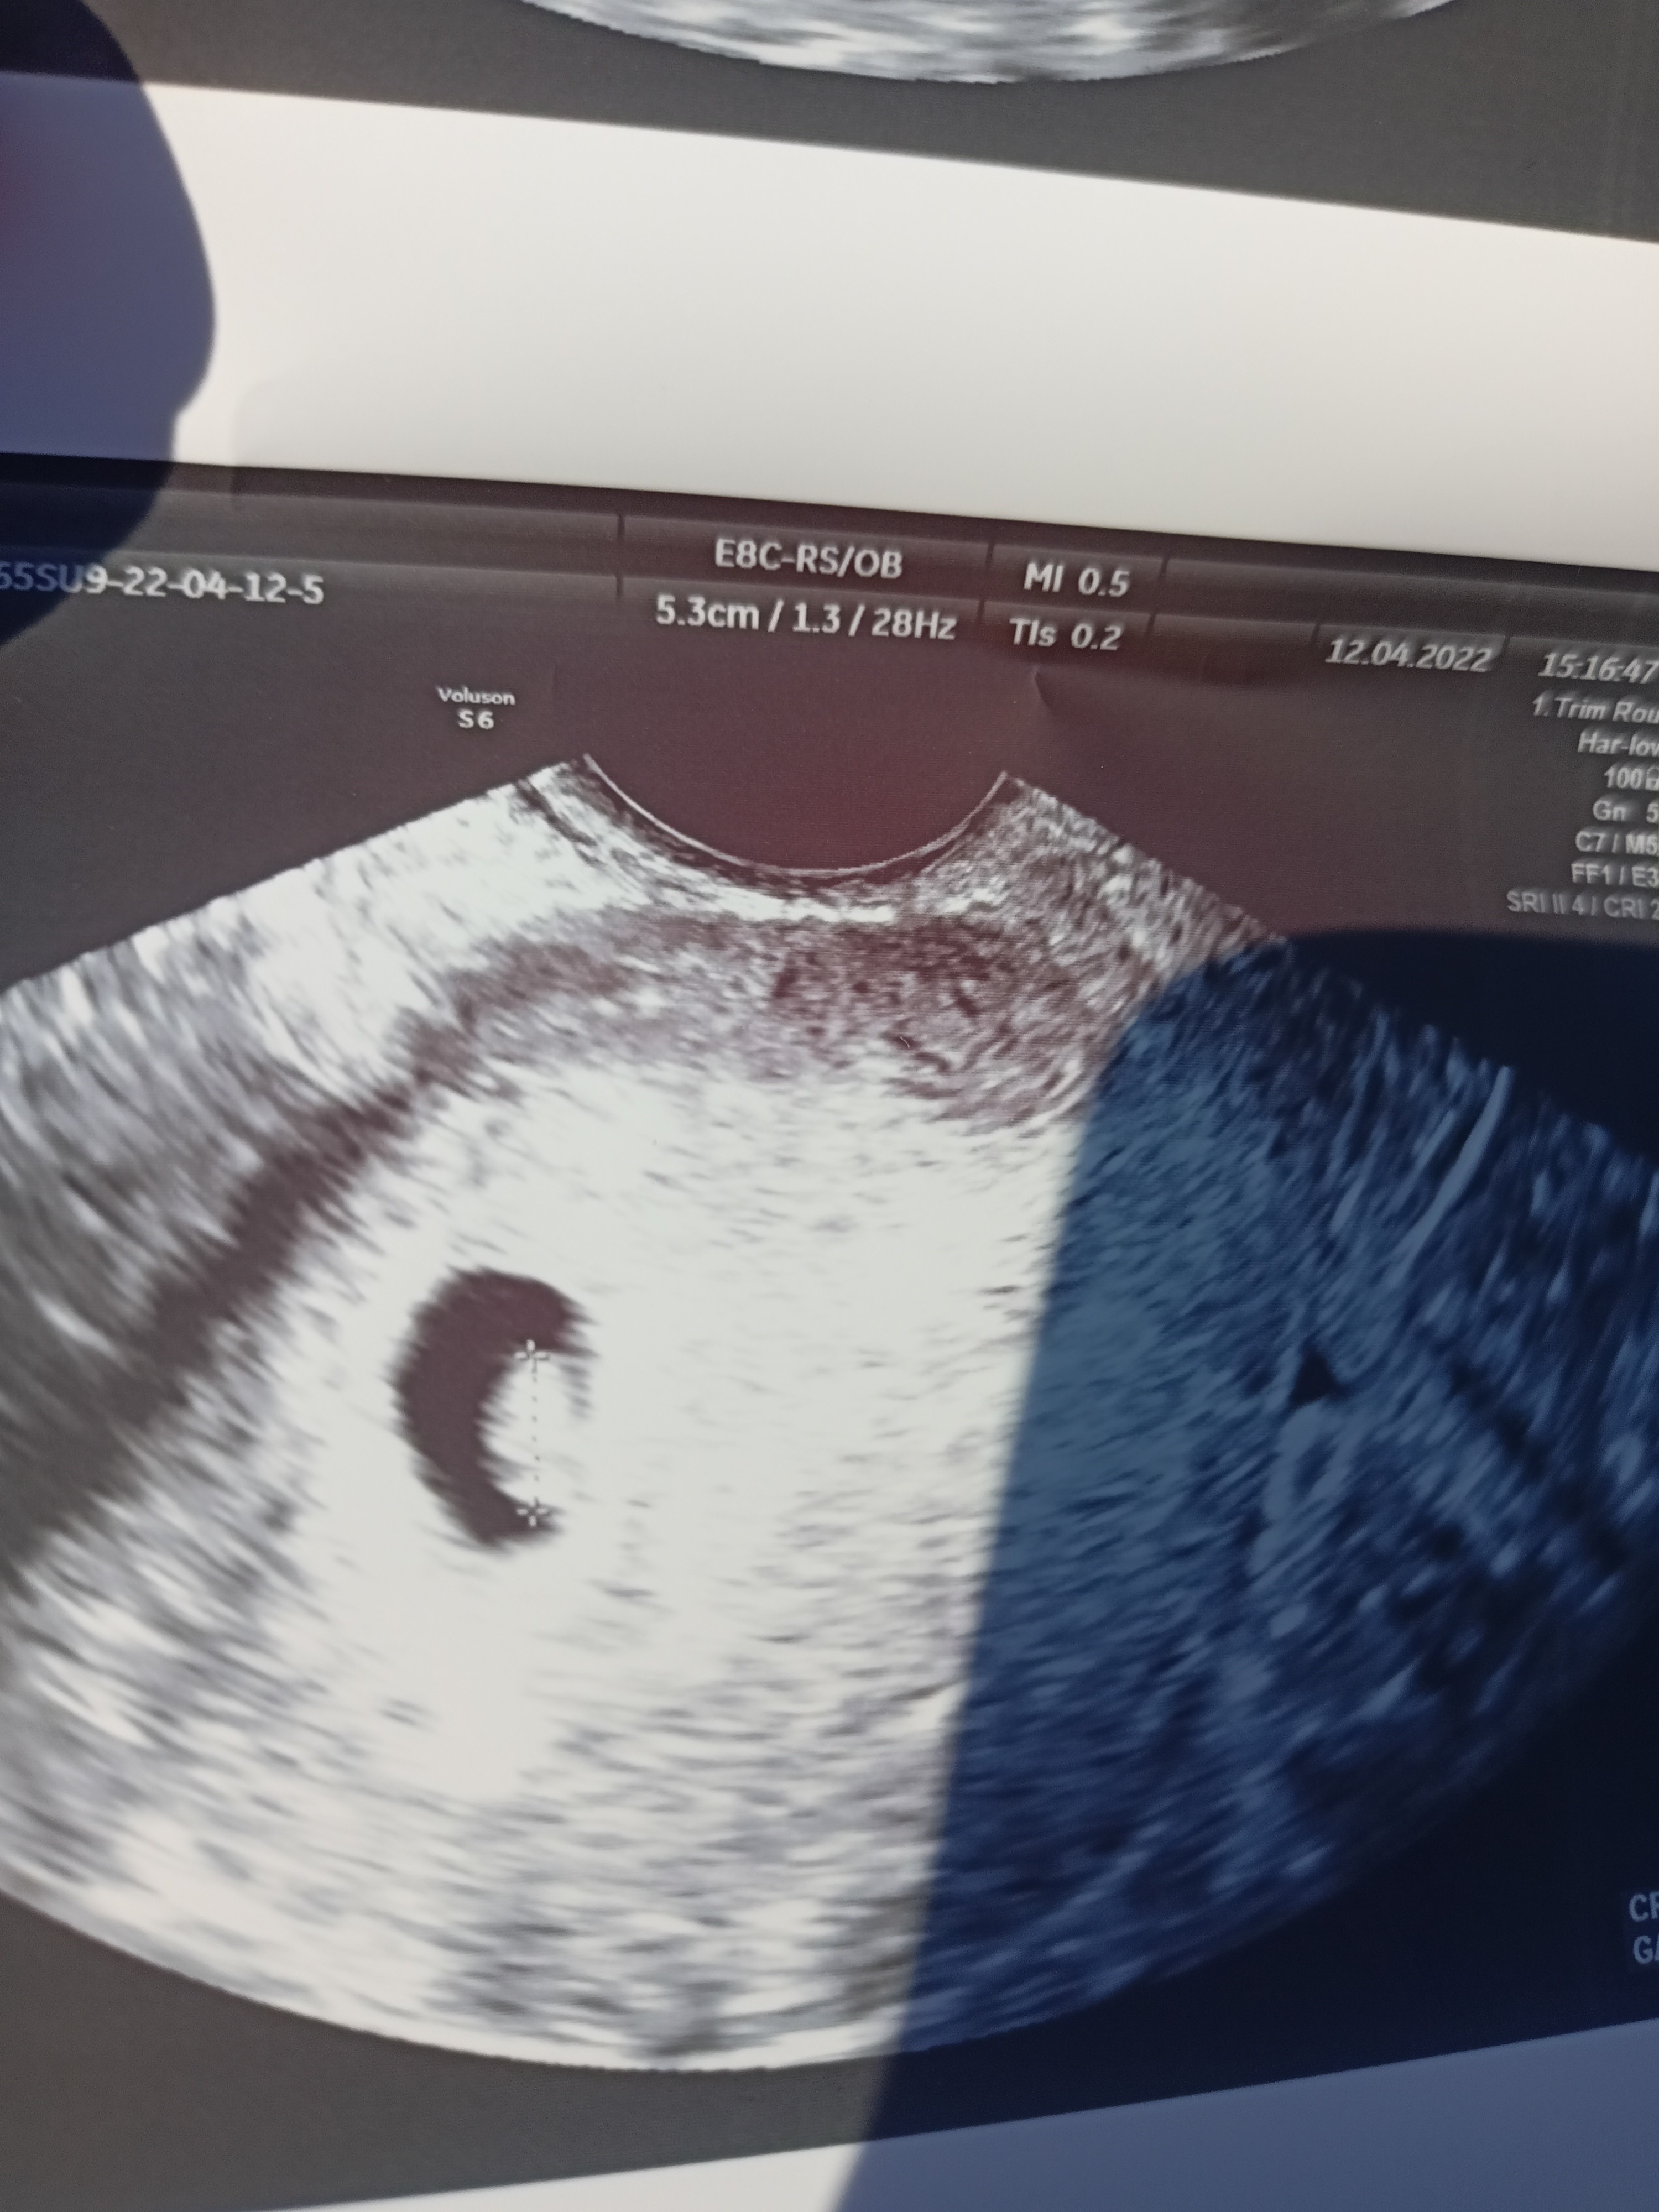

To ja naprawdę podchodzę do tego na spokojnie i czekam na wizytę

wiadomo że chce być w zdrowej ciąży, mam nadzieje że jest wewnątrzmaciczna, żywa i będzie zdrowa i trwająca do tego 38-39 tygodnia ale tak naprawdę nie mam na to wpływu. Nawet mi się czas do wizyty jakoś nie dłuży specjalnie.